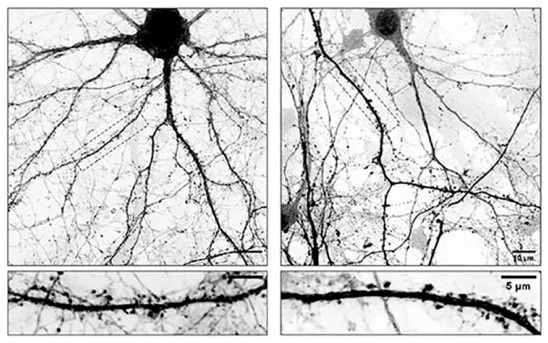

A la izquierda, neuronas normales. A la derecha, neuronas modificadas con L-Dopa.

Un equipo del CONICET, con base en el Centro de Investigaciones en Química Biológica de Córdoba (CIQUIBIC), junto a investigadores de la Universidad Grenoble Alpes, avanzó en esa dirección. El trabajo reveló que la L-Dopa no solo actuó como precursora de dopamina, sino que también interactuó con los microtúbulos, componentes esenciales del esqueleto interno de las neuronas.

Estos microtúbulos funcionaron como vías de transporte intracelular y resultaron fundamentales para mantener la comunicación entre neuronas. Los ensayos mostraron que, al incorporarse la L-Dopa en su estructura, estos “rieles” perdieron dinamismo y dejaron de ingresar correctamente a las espinas dendríticas, pequeñas prolongaciones donde se establecen las sinapsis.

Como consecuencia, las neuronas comenzaron a perder espinas dendríticas, un proceso que debilitó la comunicación neuronal. Según explicó el investigador del CONICET Gastón Bisig, esta inestabilidad sináptica podría estar vinculada a los efectos adversos que aparecieron tras años de tratamiento continuo con L-Dopa.

En relación con lo mencionado, el equipo trabajó con cultivos primarios de neuronas de ratón que fueron tratados con el fármaco bajo condiciones controladas. A partir de ese abordaje, y mediante el uso de microscopía de alta resolución y marcadores fluorescentes, los investigadores analizaron en tiempo real los cambios estructurales y la dinámica interna de las células.